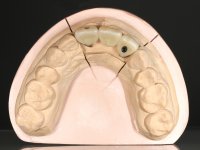

Na fase inicial, foi proposto à paciente fazer a exposição cirúrgica do implante e após avaliação clínica tomar decisões protéticas. Colocado o parafuso de cicatrização e feita a cicatrização dos tecidos moles, foi constatada uma posição inadequada do implante. Perante o dramatismo da situação foi proposto à paciente a remoção do implante e após regeneração tecidular colocar um novo implante. Esta proposta foi recusada pela paciente e foi sugerido por esta a reabilitação provisória do implante. Nesse sentido foi então feita nova proposta, desta feita, reabilitando o implante. Foi sugerido a confeção de um coto aparafusado e sobre este a colocação de uma coroa de acrílico com componente coronário e gengival. Passados 6 anos com o tratamento provisório a paciente surge na consulta com um abcesso no dente 1.1. Feita a análise clínica e imagiológica decidiu-se extrair os dentes 1.1 e 2.2, submergir o implante, colocar dois implantes no local dos 1.1 e 2.2 e fazer regeneração tecidular adequada. A temporização seria feita com uma ponte provisória de 3 elementos aderida com uma rede aos dentes vizinhos. Após osteointegração seria reabilitada definitivamente com uma ponte de 3 elementos, com infraestrutura de Zr revestida a cerâmica.

A exposição cirúrgica do implante e a colocação do parafuso de cicatrização mostrou-se uma surpresa negativa no que diz respeito à sua posição. Rejeitada a proposta de remoção do implante, avançamos para a sua reabilitação provisória. Foi feita a impressão por técnica de moldeira aberta e em laboratório foi confecionado um coto aparafusado com componente gengival e coronário e uma coroa em acrílico também com estes dois componentes. A coroa provisória foi colocada em boca até ser tomada uma decisão definitiva. Passaram 6 anos até que a paciente retorna à consulta com um abcesso no dente 1.1. Tomada a decisão de extrair os dentes 1.1 e 2.2 foi feita uma impressão para confecionar uma ponte provisória de 3 elementos com uma rede para ser aderida aos dentes adjacentes. A cirurgia foi planificada e realizada, colocando-se os dois implantes no local do 1.1 e 2.2 e o implante no local do 2.1 foi cortado com o objetivo de o submergir, simultaneamente foi feita a regeneração tecidular adequada (Trabalho Cirúrgico realizado por Dr. Manuel Neves). Durante a osteointegração a paciente utilizou a ponte provisória fixa. Foi realizada primeira impressão para a confeção de uma ponte provisória aparafusada em Zr que trabalhou durante 12 semanas os tecidos moles. A impressão definitiva foi feita com a individualização dos transferes. A reabilitação definitiva foi feita com cotos ceramizados e com uma ponte de infraestrutura em Zr revestida por cerâmica. Em virtude da inclinação do implante colocado no local do dente 1.1 a ponte exigiu fixação cimentada.